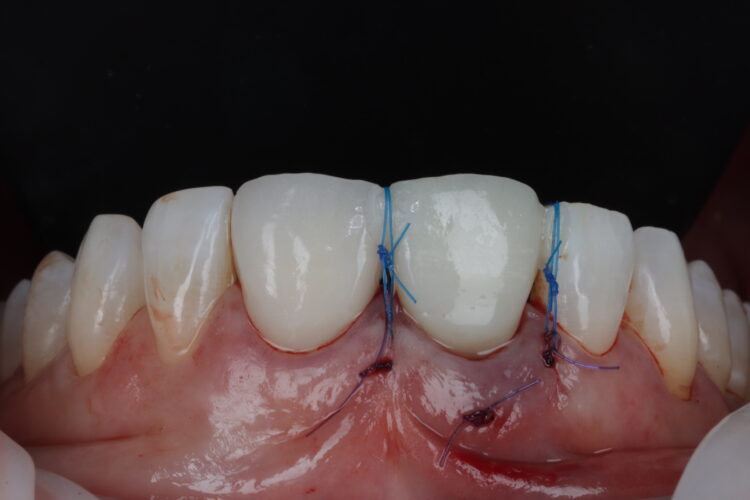

A free gingival graft was harvested from the palate, allowing enough tissue to reach between the base of each papilla and this was de-epithelialised to obtain the connective tissue. A thickness of 1mm is adequate, but in this instance, it was made intentionally thicker at the disto-buccal aspect to help plump up the papilla where bone loss was greater. The connective graft tissue was stabilised with three resorbable sutures placed, positioning the connective tissue graft 1mm below the free gingival margin.

The temporary restoration was then reintroduced and the surgical site closed tension-free. Vertical sling sutures were placed through both papillary areas over the contact points to hold the tissue up, create a prosthetic sealand to combat natural shrinkage.